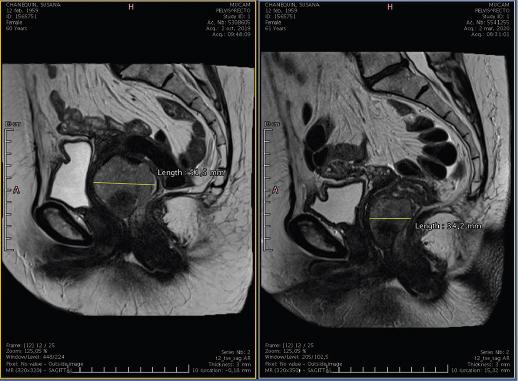

Los GIST rectales representan la tercera localización más frecuente, aunque solo suponen el 1.6-5% de todos los GIST34. No tienen síntomas específicos, por lo que frecuentemente se confunden con otras patologías anorrectales. Los síntomas más frecuentes son el sangrado (28.9%) y el dolor anal (17.8%). En ocasiones son hallazgos incidentales. La TC y la RM (Fig. 4) son muy útiles para su diagnóstico y estadificación, además de permitir determinar una posible afectación de órganos pélvicos. La ecografía endorrectal localiza el tumor y determina el tamaño y su relación con los esfínteres35,36.

Figura 4 Resonancia magnética de tumor del estroma gastrointestinal rectal que permite apreciar sus relaciones anatómicas en pelvis.

Los GIST rectales localmente avanzados, no candidatos a una cirugía de resección «de entrada», deben someterse a tratamiento neoadyuvante (Fig. 5) para reducir su tamaño y facilitar la preservación esfinteriana40,41. La combinación de neoadyuvancia y cirugía es factible en más de la mitad de los casos40,41.

Figura 5 Efectos del tratamiento neoadyuvante en tumor del estroma gastrointestinal rectal, antes (izquierda) y después (derecha) del tratamiento con imatinib, apreciándose una importante disminución del tamaño tumoral.